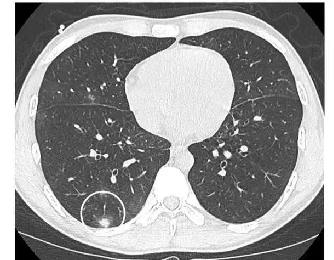

胸部CT:

SPN评估关键,薄层CT可清晰展现结节细节,如密度(实性、磨玻璃、混合性)、边缘(光滑、分叶、毛刺)、内部结构(有无空洞、钙化)等特征。如磨玻璃结节伴实性成分、边缘毛刺征、胸膜牵拉等常提示恶性可能;良性结节钙化多呈中心性、层状或爆米花状。增强CT依据结节强化程度辅助判断血供,恶性结节多呈中度至高度强化。